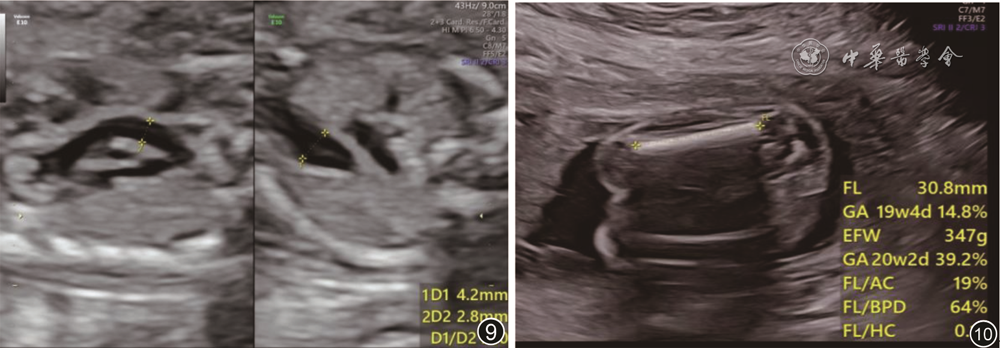

患者女性,29岁,孕4产1,2019年7月因异位妊娠行左侧输卵管切除手术。本次受孕末次月经时间为2021年1月15日,停经40 d自测尿人绒毛膜促性腺激素阳性。2021年4月20日行早孕筛查检查,估测孕周12周0天,颈项透明层厚度1.7 mm,股骨长6.3 mm(图1);2021年5月19日孕16周行常规超声检查时发现胎儿膀胱横断面双侧脐动脉未显示,股骨长15 mm(图2)。2021年6月18日孕20周行胎儿超声心动图检查时发现胎儿膀胱横断面未见左右脐动脉(图3),脐带游离段呈“吕”字形(图4);腹主动脉起始处向左上腹发出一粗大血管(图5),并于脐孔水平、脐孔内侧扭曲后出腹壁,其内部测及类似脐动脉多普勒血流波形(图6);腹主动脉分叉处下段明显变细(图7),另见左侧肾上腺平躺(图8),左侧肾窝未见肾回声,心脏肺动脉总干/主动脉比值为1.55(图9),胎儿股骨长31 mm(图10)。超声提示:单脐动脉并脐动脉腹内段走行异常;左肾缺如;心脏肺动脉总干/主动脉比值偏大。2021年7月1日孕22周大畸形筛查与前次检查结果相同,其余结构未见明显异常。羊水穿刺染色体核型分析结果正常。患者产前诊断咨询后决定终止妊娠,于2021年7月6日入院引产,7月7日胎儿娩出,外观未见明显异常,未行病理解剖。

图10 胎儿20周超声检查显示股骨长度